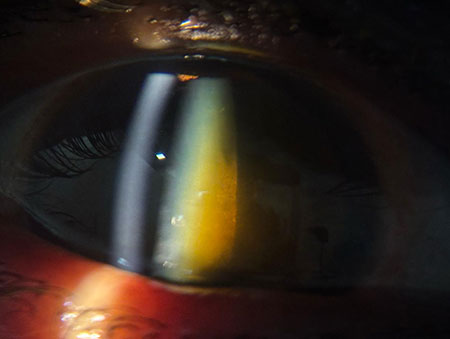

Chalazion – Successful Surgical Management At Vivaan ENT & Eye Clinic, we regularly manage eyelid conditions such as chalazion with safe, effective, and minimally invasive procedures. Recently, a patient underwent chalazion incision and curettage, performed by Dr. Veena Karkhele (Garje) under local anesthesia. The procedure was completed smoothly, and the patient had an excellent post-operative recovery with significant relief from swelling and discomfort.